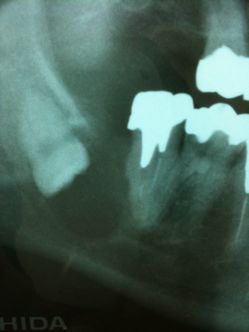

平成6年の時の写真です。

右下に親知らずがありますが、症状もなく放置しております。

手前の銀歯の適合も良く有りませんが、これも症状がなく放置しております。

それから17年が経過しました。

親知らずはまるで手品のように傾いています。ほぼ逆さまに近い状態です。

レントゲンで黒くなっている透過像を見て「悪性腫瘍では?」という最悪の事態も考えました。

紹介先の日鋼記念病院で入院。抜歯を含む手術を行いました。

悪性腫瘍でなくホッとしました。

平成6年に説得して抜いていれば、、、悔やまれます。